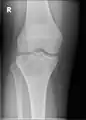

A variety of imaging studies can be used to diagnose chondroblastoma, with radiographs being the most common.[10][8] Laboratory studies are not considered useful.[14] Classical chondroblastoma (appearing on long bones) appears as a well-defined eccentric oval or round lytic lesion that usually involves the adjacent bone cortex without periosteal reaction.[10][13] A sclerotic margin can be seen in some cases.[10][13] For long bone chondroblastomas the tumor is typically contained to the epiphysis or apophysis but may extend through the epiphyseal plate.[10][13] Chondroblastomas are usually located in the medullary portion of bones and can, in some cases, include the metaphysis.[10][13] However, true metaphyseal chondroblastomas are rare and are typically the result of an extension from a neighboring epiphyseal legion.[10][13] Most lesions are less than 4 cm.[10] A mottled appearance on the radiograph is not atypical and indicates areas of calcification which is commonly associated with skeletally immature patients.[10] Additionally, one-third of all cases involve aneurysmal bone cysts which are thought to be the result of stress, trauma or hemorrhage.[10] In cases involving older patients or flat bones, typical radiographic presentation is not as common and may mimic aggressive processes.[10][13]

Other imaging techniques involve computed tomography (CT), magnetic resonance imaging (MRI), and bone scans, which may be helpful in determining the anatomical boundaries, associated edema, or biological activity of the chondroblastoma, respectively.[8][10] MRI studies may show extensive oedema around the lesion and show variable T2 signal intensity.[15]